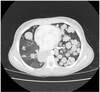

How does Interstitial Pneumonia appear radiographically?

-“Honeycomb Lung” as seen on CT -Interstitial tissue thicker between all of the alveoli (inflammation between the air spaces) -Tissue between alveoli more visible ## Footnote No heavy mucus, bronchiectasis as seen in CF

What pathology is seen here?

Interstitial Pneumonia

52